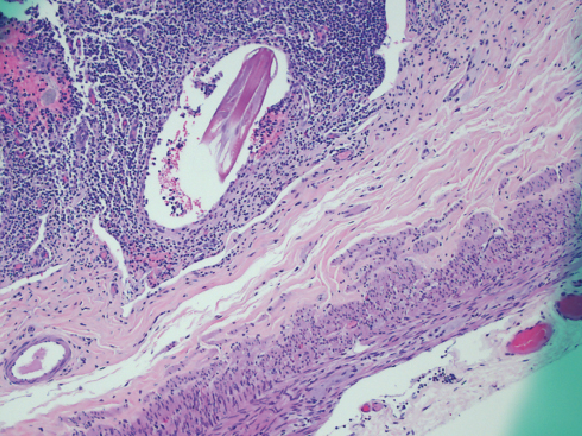

hepatic cirrhosis

Ahmad Alsafadi, MB, BCh; Imad Absah, MD; Mounif El-Youseff, MD

A 15-year-old girl presented with diarrhea, abdominal pain, and hematochezia.